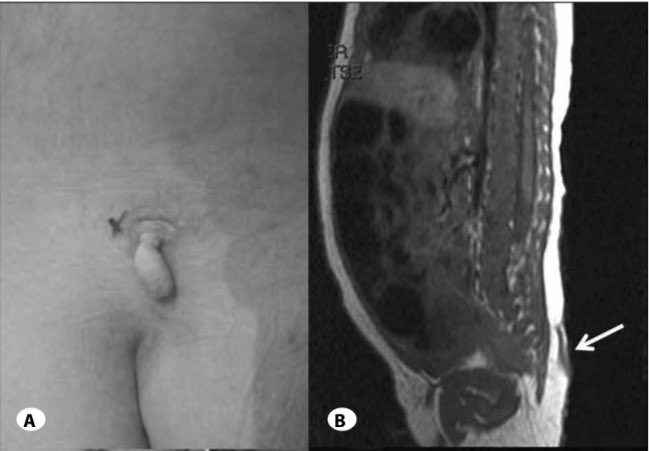

الذيل البشري: هو مصطلح لوصف (نتوءات مغطاة بالجلد) في المنطقة القطنية العجزية والعصعصية من الظهر، ويكون شكلها مشابه لذيول الحيوانات

وقد تم تسجيل الحالة للمرة الأولى علمياً عام 1892 كما في الصورة

وصولاً للعام 1984 في دراسة تم فحص 33 حالة وتصنيف الذيول فيها الى نوعين:

1. ذيول حقيقية: وصفوها بقايا ذيل الجنين علماً انها تفتقر للعظم والغضاريف والحبل الشوكي

2. ذيول كاذبة: وصفوها بتشوه (استطالة شاذة) في الفقرة العصعصية

وصولاً للعام 2005 مع تقدم العلم وتقنيات التصوير المقطعي والإشعاعي

تم تحديد الأهمية المرضية وحالات التشوه الشاذة المرتبطة بالعمود الفقري مع العمل على صياغة استئصال جراحي

وتبيان السبب بكونه اضطراب في الأعصاب الثانوية و/أو انحسار في برعم طرف الجنين